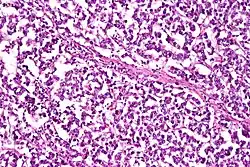

A micrograph view of dysgerminoma, showing actively dividing lobulated nuclei.

Dysgerminomas are comparable to testicular seminomas and account for approximately 32- 37% of all OGCTs.[1] They are particularly prominent in individuals with dysgenic gonads of 46, XY pure gonadal dysgenesis patients.[1] Based on gross examinations, dysgerminomas are characterized by having a ‘solid, lobulated, tan, flesh-like gross appearance with a smooth surface'.[1] Microscopically, the cellular structure is distinguished by a round-ovoid shape containing ample eosinophilic cytoplasm and an irregularly shaped nuclei.[1] The uniformly positioned cells are separated through the fibrous strands and lymphocytic infiltration is commonly observed.[4]